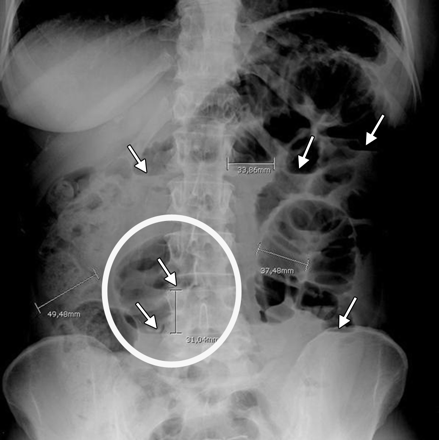

Tắc ruột phân su xảy ra khi có một cản trở trong quá trình di chuyển của phân qua ruột non và ruột già. Điều này có thể xảy ra do nhiều nguyên nhân khác nhau, bao gồm sỏi ruột, u xơ ruột, viêm ruột, hoặc các vấn đề về cơ bên trong ruột. Khi tắc ruột phân su xảy ra, các triệu chứng thường bao gồm đau bụng, buồn nôn, nôn mửa, khó tiêu, và khó đi ngoài.

Đối với những trường hợp tắc ruột phân su nghiêm trọng và không thể điều trị bằng phương pháp không phẫu thuật, phẫu thuật là một lựa chọn hợp lý. Phẫu thuật có thể giúp loại bỏ cản trở trong ruột và khôi phục sự thông suốt của quá trình tiêu hóa. Các phương pháp phẫu thuật điều trị tắc ruột phân su có thể được áp dụng tùy thuộc vào nguyên nhân cụ thể của tắc ruột.